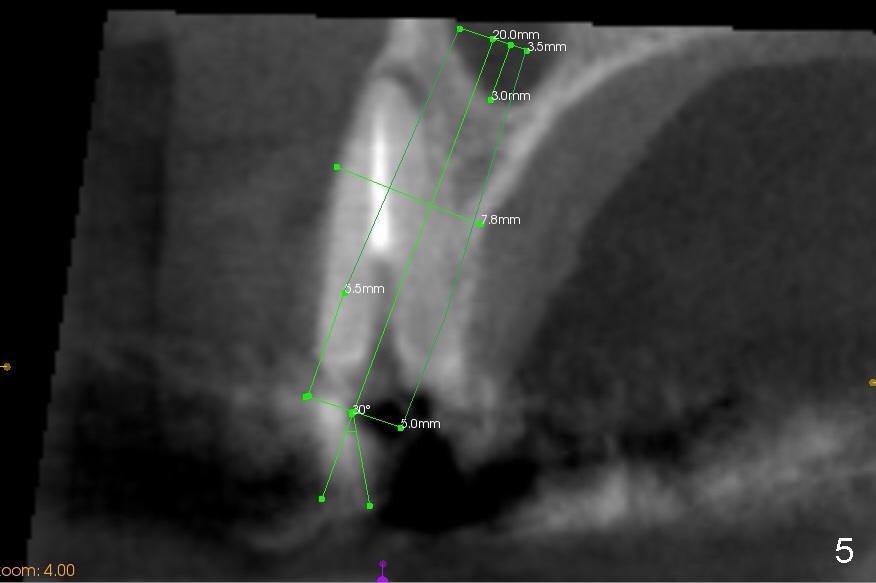

CBCT studies reveal that the implant perforates the buccal plate at the site of #7 and that there is still enough bone to support 3.0x17 mm one piece implant (Fig.2,3).  There is limited bone apical to the tooth #6.  The implant should be at least 17 mm for bone level and 14 mm for tissue level (Fig.4) or preferably 20 mm with sinus lift (Fig.5).  The diameter will be 4.5 mm (Fig.6) or 5 mm (Fig.4.5).